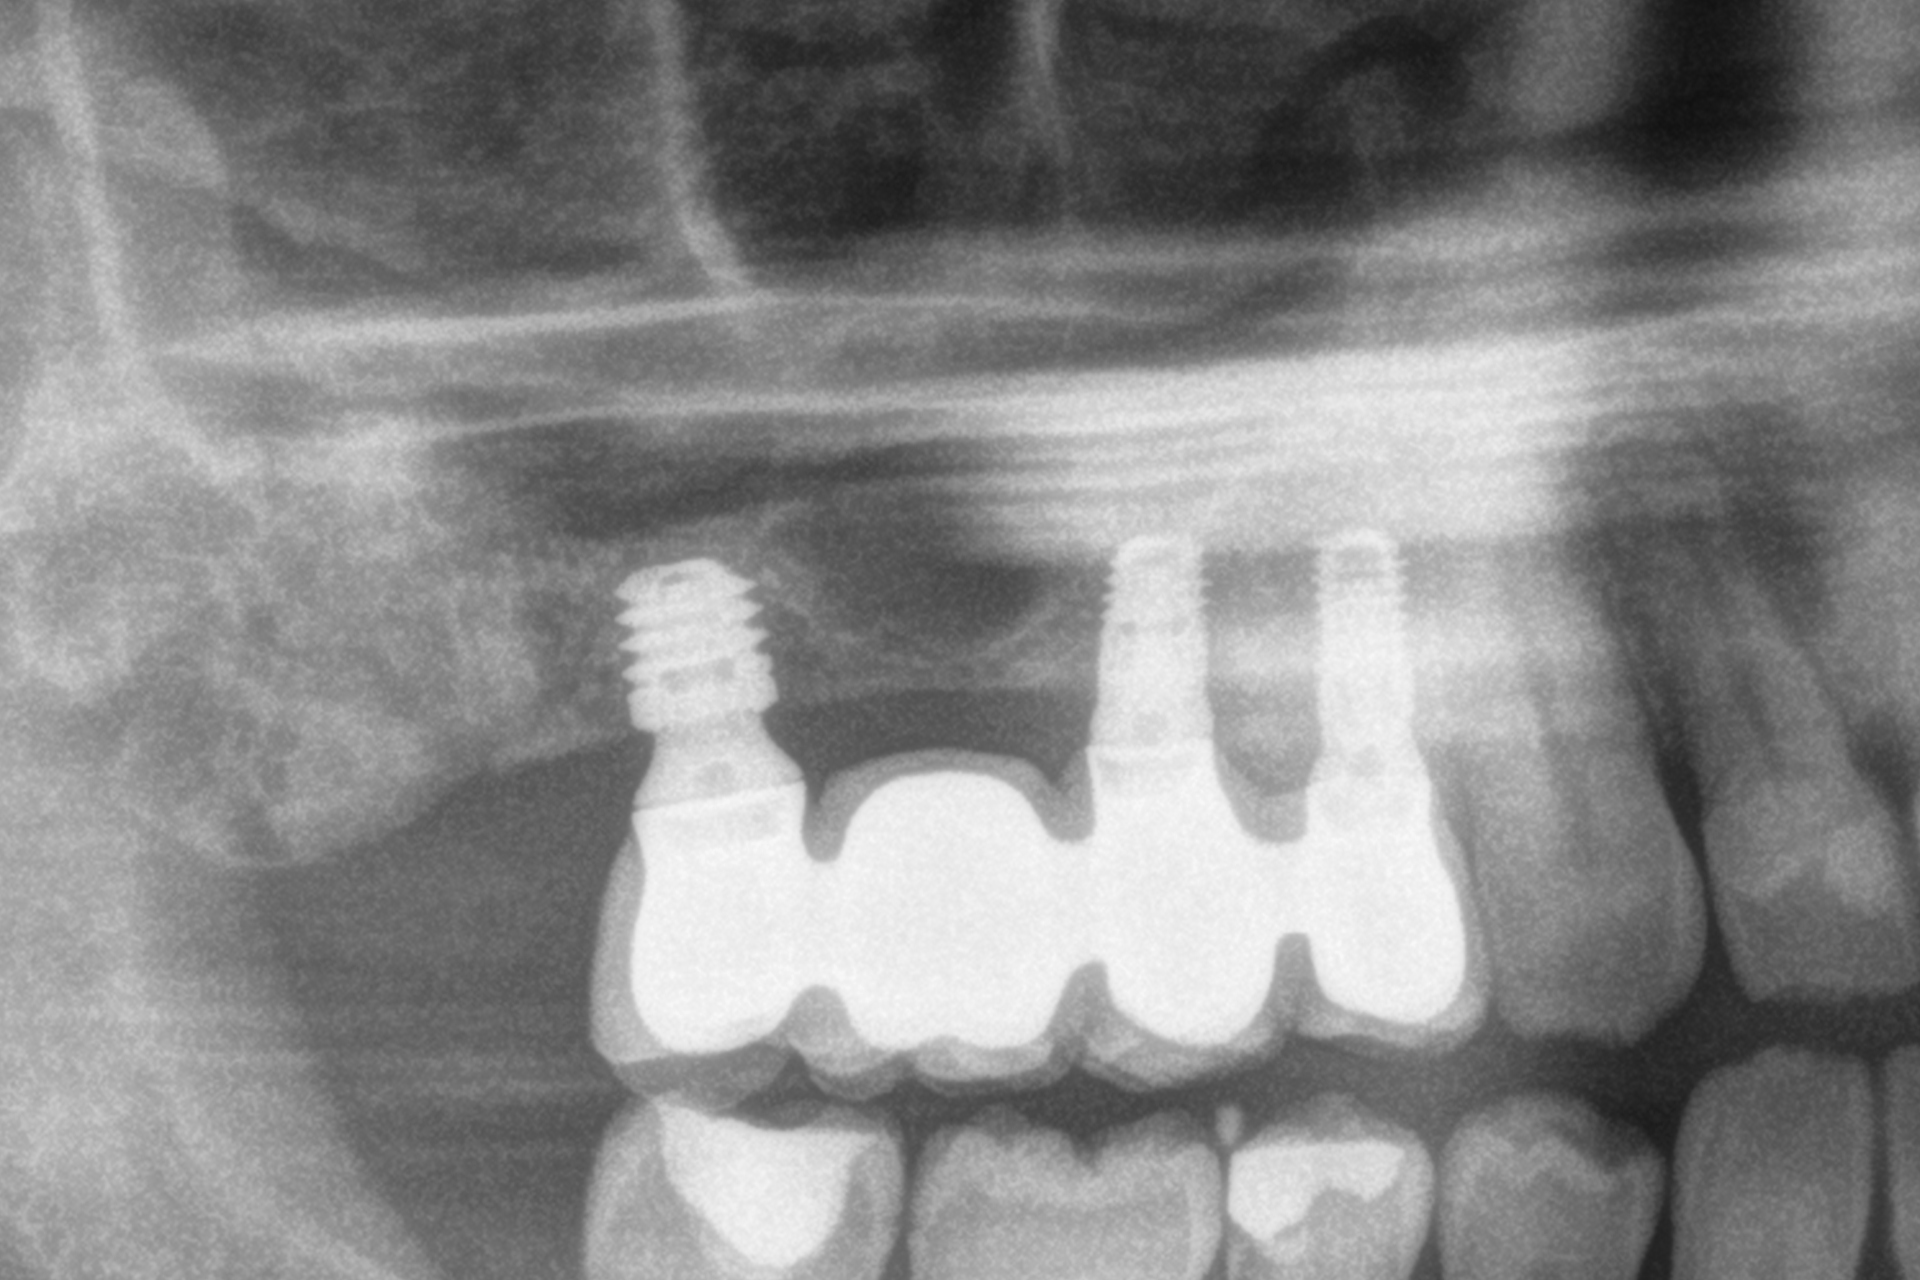

Tutti gli impianti sono stati caricati entro 24 ore dall’inserimento mediante protesi provvisorie in resina a carico immediato, realizzate con strutture a barra articolata. L’analisi dei diversi tipi di protesi ferulizzate ha evidenziato una predominanza delle riabilitazioni parziali. Il gruppo più numeroso era costituito dalle protesi supportate da due impianti e due elementi dentari, pari al 33,3% dei casi, seguito dalle protesi complete, presenti nel 19,4% dei pazienti. Altri disegni protesici sono stati utilizzati con frequenze comprese tra l’8,3% e il 16,7%, riflettendo l’adattamento del piano terapeutico alle specifiche condizioni anatomiche di ciascun paziente, mantenendo in tutti i casi la ferulizzazione rigida degli impianti come principio biomeccanico fondamentale (Figura 1).

In 19 impianti sono state eseguite procedure complementari contestualmente all’inserimento implantare: in due casi rigenerazione verticale con osso autologo da fresaggio associato a PRGF-Endoret; in 11 casi rialzo del seno mascellare transalveolare con osso autologo e PRGF-Endoret; in sei casi sovracorrezione vestibolare mediante osso autologo e PRGF-Endoret, associando uno strato di biomateriale (idrossiapatite bovina) per ridurre il riassorbimento volumetrico. Quattro impianti da 4,5 mm sono stati ferulizzati ad altri impianti della stessa lunghezza, per un totale di otto impianti ultra-corti ferulizzati tra loro, configurando ponti supportati da tre impianti. La protesizzazione definitiva è stata eseguita tra tre e nove mesi dopo il carico immediato. Le protesi definitive erano in metallo-ceramica nell’80,6% dei casi e in resina con struttura metallica nei restanti.

Al termine del follow-up, la perdita ossea crestale media è stata di 0,73 ± 0,18 mm in mesiale e di 0,85 ± 0,34 mm in distale. Alcuni casi clinici rappresentativi sono illustrati nelle Figure 2-10.